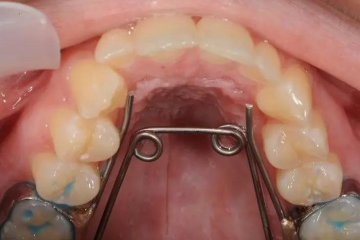

Thế nào là nong hàm bằng dây cung? và các kỹ thuật nong hàm hiện nay

Thế nào là nong hàm bằng dây cung? Nong hàm bằng dây cung là kỹ thuật phổ biến được ứng dụng trong nha khoa nhằm mục đích nới rộng vòm...